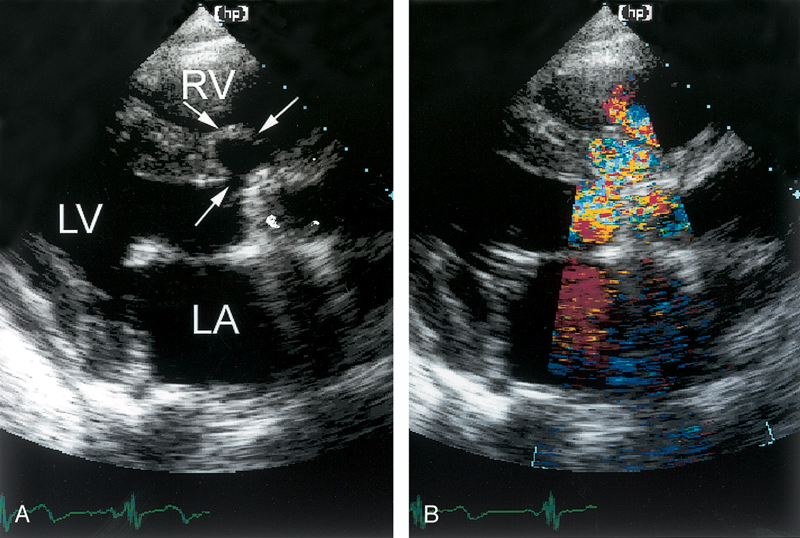

فحوصات تشخيصية لبعض امراض القلب والشرايين التاجية